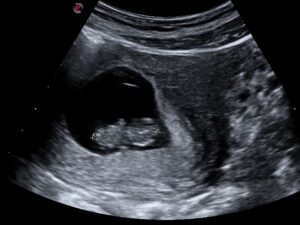

7 Weeks

At Approximately 7 weeks after the 1st day of the last menstrual period we will see a small fetus with a heartbeat in the gestation sac.